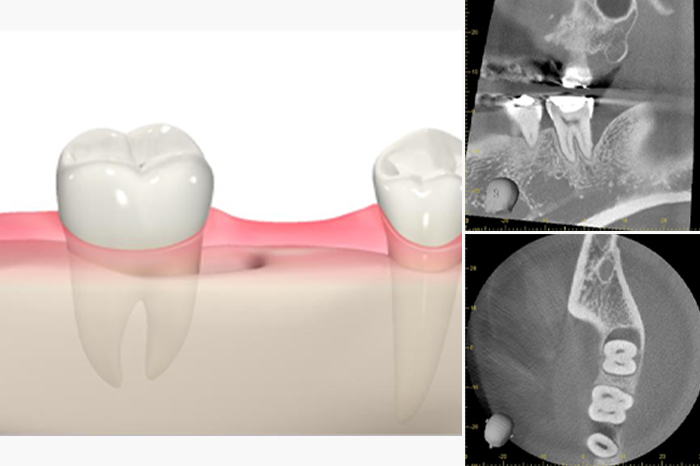

再生治療

近年、再生治療が保険でも導入されました。歯周病になって骨が溶けても、一部分骨が戻ってくるというのが再生治療になります。保険治療ではリグロスというジェル状の薬を骨と歯ぐきの間に入れることで骨が再生してくるのですが、適応症が限られています。

図1のように骨の形態が薬が維持できないような形ですと、ほぼ流れ出てしまい、効果がでないからです。

再生治療で使用する薬が患部で維持できず効果がない場合の歯と歯ぐきのイメージ

図2のような皿状の形態ですと、薬も維持しやすく、効果がでやすいのです。

再生治療で使用する薬を患部で維持で効果がないでやすい場合の歯と歯ぐきのイメージ

では形態が悪いと再生治療ができないのかと言われるとそうではありません。

自費治療にはなりますが、人工骨を使用したり、薬を維持させるためのメンブレンやチタンメッシュを用いて再生を促す事ができますので、ご興味がある方、歯を絶対残したい方は私どもにご相談ください。